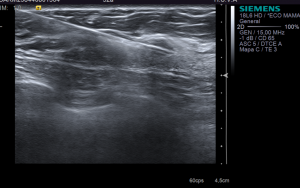

DIAGNÓSTICO FINAL: fibroadenoma esclerosado con calcificaciones gruesas.

Los fibroadenomas son los tumores mamarios más frecuentes en mujeres jóvenes. Se observan como nódulos bien circunscritos de morfología ovalada o lobulada. En las mujeres con edades superiores a 40 años pueden presentar calcificaciones groseras o en palomitas de maíz.

Anatomopatológicamente, el fibroadenoma es una tumoración fibroepitelial benigna donde el componente fibroso intralobulillar rodea o distorsiona a los conductos.